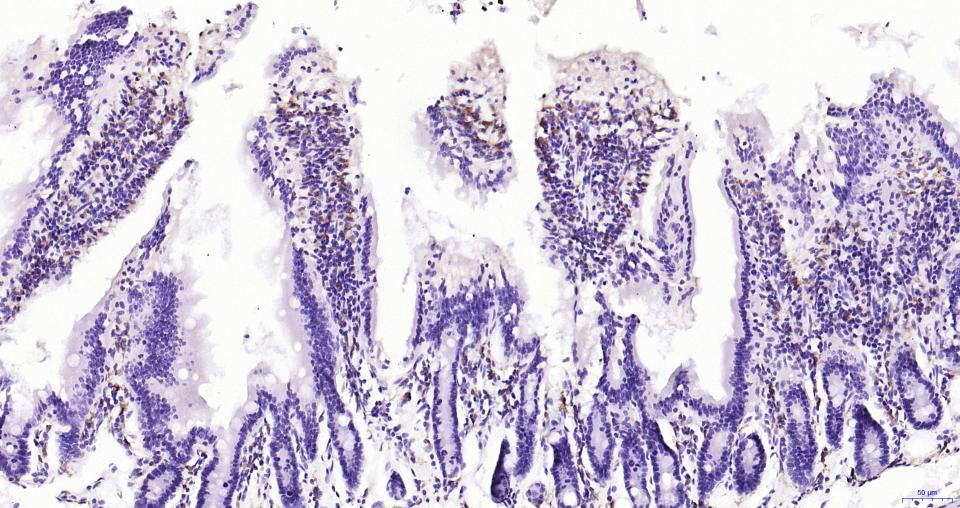

| 英文名称 | AIF1 / Iba1 Rabbit pAb |

| 中文名称 | 离子钙接头蛋白抗体 |

| 产品应用 | WB=1:500-1000, IHC-P=1:100-500, IHC-F=1:100-500, IF=1:100-500 Not yet tested in other applications. |

| 交叉反应 | Human, Mouse, Rat |

| 背景资料 | Allograft Inflammatory Factor-1 (AIF1)or ionized calcium-binding adaptor molecule 1 (Iba1) is expressed selectively in microglia/macrophages and is a Ca2+-binding peptide produced by activated monocytes and microglial cells. It has been suggested that AIF1 expression is associated with chronic inflammatory processes. AIF1 is expressed by activated monocytes and might participate in a variety of pathogenic processes in the mammalian brain and in chronic transplant rejection. It has been shown to be expressed early and persistently in chronically rejecting cardiac allografts but not in cardiac syngrafts and host hearts. |

| {IHC-P} | {1:100-500} |